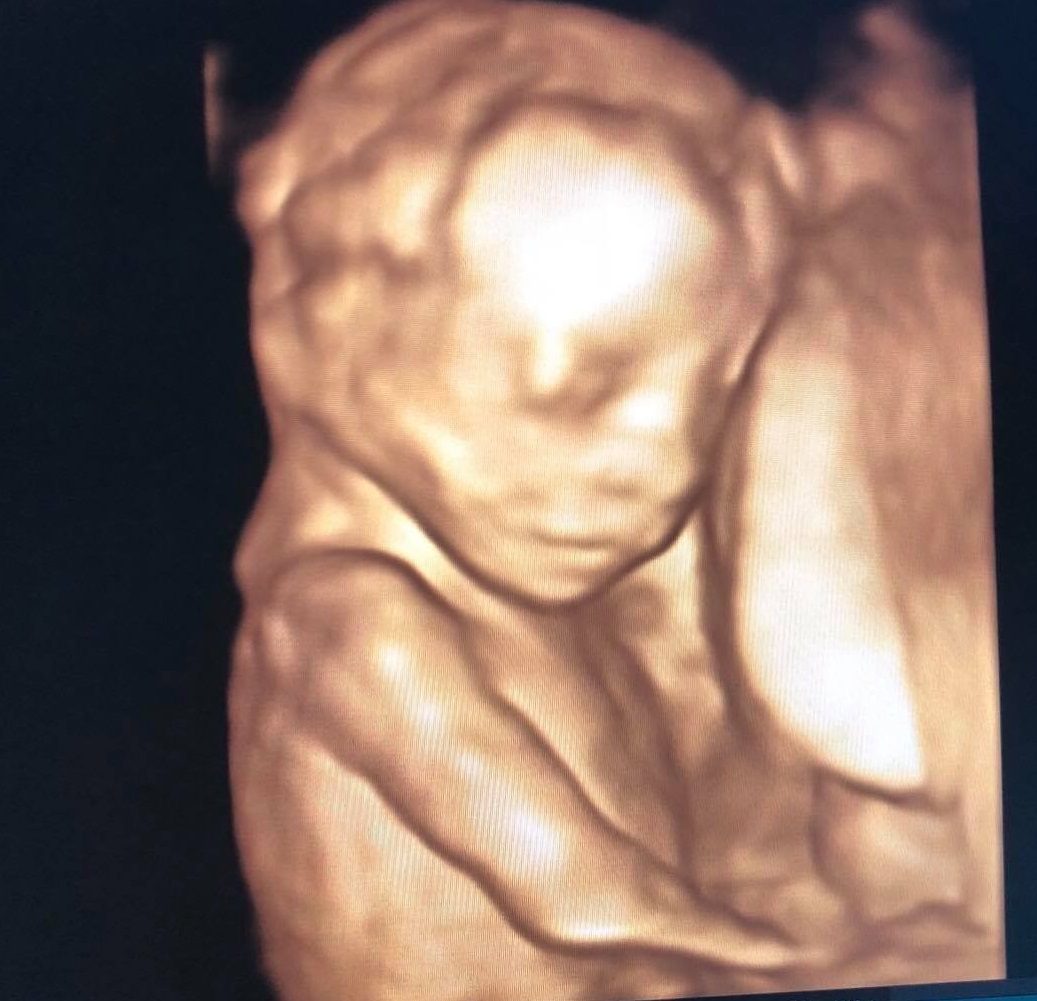

Tầm soát dị tật thai nhi và xét nghiệm thai kỳ

Khi đi siêu âm thai nhi 19 tuần tuổi, thai phụ cần thực hiện các xét nghiệm sàng lọc dưới đây:

Tầm soát dị tật thai nhi bằng siêu âm 4D, 5D. Phương pháp này chẳng những giúp mẹ được nhìn thấy bé yêu mà còn cho biết các chỉ số phát triển của thai nhi và phát hiện những bất thường nếu có.